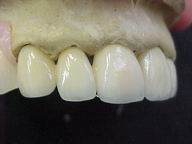

Reabilitação funcional e estética em ambas as arcadas

com próteses fixas e removíveis de encaixe de precisão.

ANTES